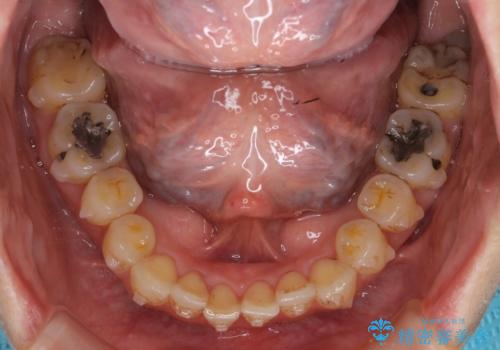

途中再評価を行い、矯正用のミニスクリューを用いて奥歯を遠心移動し、前歯の出っ歯傾向を改善しました。

左上12の段差についてはここまで直すのにもかなり時間がかかりました。インビザライン単独では限界があると説明し、ワイヤーの部分矯正もご提案しましたが、患者様のご希望によりインビザラインでできるところまで頑張るということで4回ほどリファインメントを行いました。